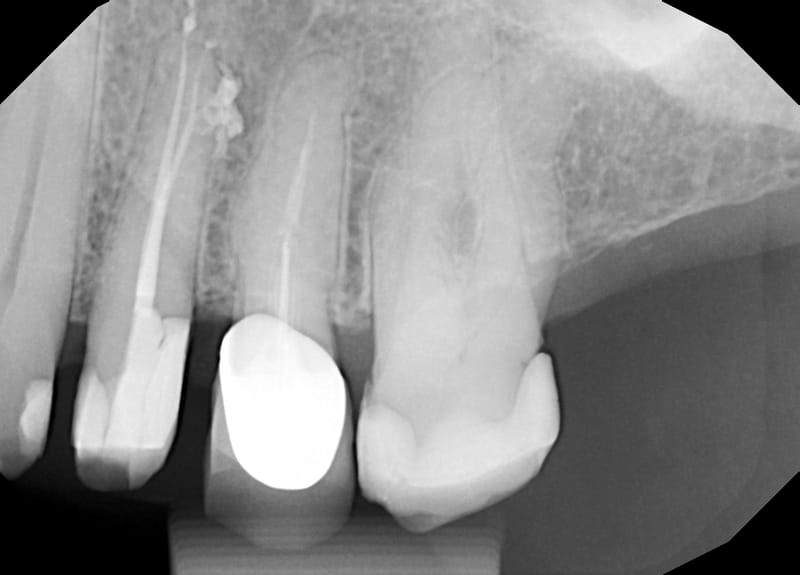

Leczenie powtórne d.14